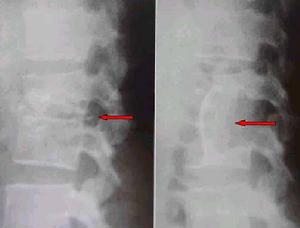

(3)、X線及CT檢查:發病2周內普通X線片可無任何異常發現,斷層攝影或CT掃描,有時可見有局限性骨質吸收或斑點狀骨質破壞。隨著病變的進展,軟骨板可出現破壞,椎體邊緣模糊呈毛刷狀。繼而椎旁軟組織腫脹,椎間隙變窄骨密度增加,骨質硬化,骨橋形成等,在早期影像學不能作出明,確診斷時應及時在CT引導下作診斷性穿刺。